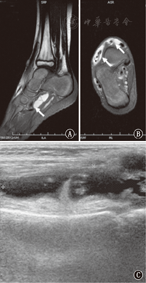

查体:双侧踝关节囊肿样肿胀,无明显触痛,有波动感。无明显发热,左臂皮肤有苔癣样皮疹,右侧眼球结膜充血(图2)。实验室检查:C反应蛋白(CRP) 2.9 mg/L(正常值≤10 mg/L);红细胞沉降率(ESR)20 mm/1 h(正常值0~15 mm/1 h);免疫球蛋白IgE 0.5×103 IU/L(正常值≤0.11×103 IU/L);免疫球蛋白IgM 1.09 g/L(正常值0.6~2.5 g/L);免疫球蛋白IgG 9.75 g/L(正常值7.0~17.0 g/L);免疫球蛋白IgA 2.10 g/L(正常值0.7~3.8 g/L)。肺部CT显示两肺纹理稍紊乱,关节彩超及MRI提示双侧膝关节及左侧踝关节积液(图3)。

注:A、B:磁共振成像结果显示右踝关节周围软组织内囊性病变(箭头示);C:彩超结果显示右膝关节髌上囊积液,囊壁毛糙增厚 A,B:soft tissue cystic lesions of magnetic resonance imaging scan of the right ankle joint(marked by white arrow);C:ultrasonography of the right knee showed effusion and synovial thickening